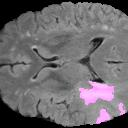

Weakly Supervised Semantic Segmentation (WSSS) relying only on image-level supervision is a promising approach to deal with the need for Segmentation networks, especially for generating a large number of pixel-wise masks in a given dataset. However, most state-of-the-art image-level WSSS techniques lack an understanding of the geometric features embedded in the images since the network cannot derive any object boundary information from just image-level labels. We define a boundary here as the line separating an object and its background, or two different objects. To address this drawback, we are proposing our novel ReFit framework, which deploys state-of-the-art class activation maps combined with various post-processing techniques in order to achieve fine-grained higher-accuracy segmentation masks. To achieve this, we investigate a state-of-the-art unsupervised segmentation network that can be used to construct a boundary map, which enables ReFit to predict object locations with sharper boundaries. By applying our method to WSSS predictions, we achieved up to 10% improvement over the current state-of-the-art WSSS methods for medical imaging. The framework is open-source, to ensure that our results are reproducible, and accessible online at https://github.com/bharathprabakaran/ReFit.